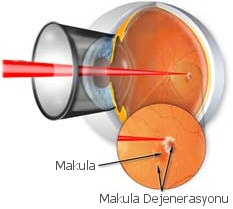

Göz küresinin arka duvarında bulunan retina tabakasının merkezine "Makula" ismi verilir. Makula bölgesinin düz bakıldığında cisimleri ayrıntılı ve net olarak görmede önemli bir işlevi bulunur. Bu bölgede bulunan fotoreseptör hücrelerinin ilerleyici kaybı ile oluşan bozulma Makula Dejenerasyonu olarak adlandırılır ve halk arasında "Sarı Nokta Hastalığı" olarak bilinir. İleri yaşlarda görme kaybının en önemli sebeplerindendir.Sarı nokta hastalığı için risk faktörleri nelerdir?

Kuru Tip Makula Dejenerasyonu

Yaş Tip Makula Dejenerasyonu